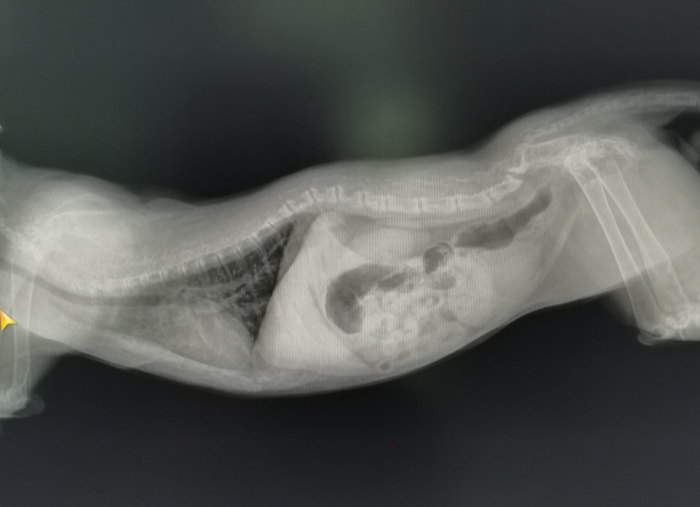

Основная проблема в том, что это абсолютно несбалансированное питание, что для котят, что для взрослых животных. В том числе, в мясе сильный перевес в сторону фосфора и недостаток кальция. Для котят этот фактор критический, фосфор начинает вымываться из костей, они истончаются, появляются деформация скелета, хромота и спонтанные переломы, а также другие симптомы, в том числе неврологические. Простыми словами – развивается рахит, а на рентгене мы видим деформированные и прозрачные косточки.

Котенок со вторичным гиперпаратиреозом (рахит) и взрослый кот с его последствиямм

Если с котятами, вовремя обратившимися в клинику, ещё можно успеть поработать и исправить ситуацию, то вот со взрослыми животными, когда зоны роста уже закрыты, сделать ничего нельзя. У таких животных могут быть недоразвитый узкий таз, из-за которого начинаются проблемы с дефекацией, а затем и из этого выливается много проблем; может быть лордоз (прогибание вниз) грудного отдела позвоночника (как на втором фото), который вызывает затрудненное дыхание, проблемы с сердцем, боли в спине и многое другое. Жизнь таких животных нельзя назвать беззаботной и счастливой.